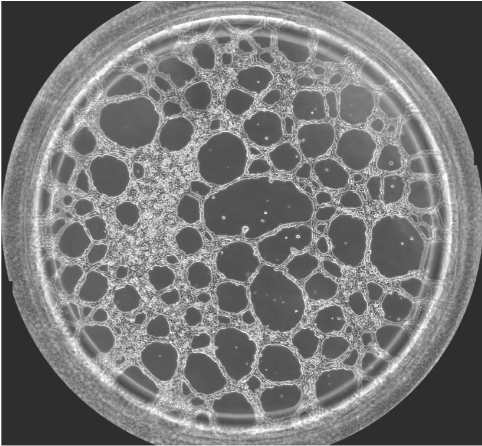

圖一 血管生成鏡檢圖

無論原發(fā)性腫瘤還是繼發(fā)性腫瘤,一旦生長直徑超過1~2 mm,都會(huì)有血管生成。這是由于腫瘤細(xì)胞自身可分泌多種生長因子,誘導(dǎo)血管生成。多數(shù)惡性腫瘤的血管生成密集且生長迅速。因此,血管生成在腫瘤的發(fā)展轉(zhuǎn)移過程中起到重要作用,抑制這一過程將能明顯阻止腫瘤組織的發(fā)展和擴(kuò)散轉(zhuǎn)移。于是體外的血管生成實(shí)驗(yàn)就能很好的模擬腫瘤的血管發(fā)生過程,并且適合研究藥物對這一過程的影響實(shí)驗(yàn)。本實(shí)驗(yàn)以HUVEC細(xì)胞為例,介紹這一實(shí)驗(yàn)的詳細(xì)過程。